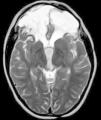

Antecedentes personales sin interés, salvo un TCS tras la caída de un televisor en la cabeza a los 4 años. En urgencias presentaba puntuación Glasgow de 7/15, por lo que se realiza una TC craneal, evidenciando estallido craneal con múltiples fracturas, contusión hemorrágica frontal bilateral y hemorragia ventricular y subaracnoidea traumáticas (fig. 1). Permaneció ingresada en Cuidados Intensivos Pediátricos durante 28 días. Entre las complicaciones que presentó durante el ingreso destacan hipertensión intracraneal, coma, crisis diencefálicas, diabetes insípida (DI), secreción inadecuada de hormona antidiurética (SIADH), infecciones del tracto urinario y respiratorio, e hiperglucemia. Al alta presentaba parálisis óculo-motora, inestabilidad de la marcha y trastorno de la memoria y del aprendizaje.